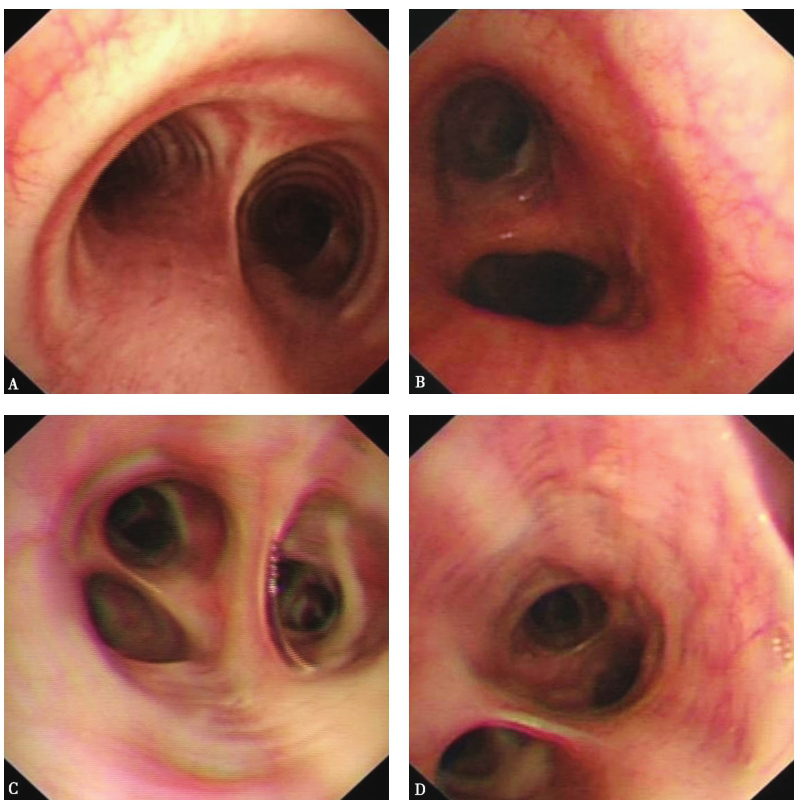

支气管镜检查,镜下见气管、主支气管和各叶段支气管管腔通畅,黏膜光滑,未见出血、新生物(图14)。左肺舌叶BALF涂片见多核巨细胞(图15A),细胞分类示多核巨细胞10%、嗜酸性粒细胞15%、组织细胞60%、淋巴细胞15%,未找到恶性肿瘤细胞,抗酸杆菌涂片阴性;在右肺下叶刷片,亦见到少数多核巨细胞(图15B)。右肺下叶经支气管肺活检病理示送检肺组织内见肺泡隔纤维组织增生、慢性炎症细胞浸润,部分肺泡腔内见融合的组织细胞(多核巨细胞)(图16)。

图14支气管镜检查镜下表现

A.气管隆嵴;B.左主支气管;C.右上叶支气管;D.右下叶基底段支气管